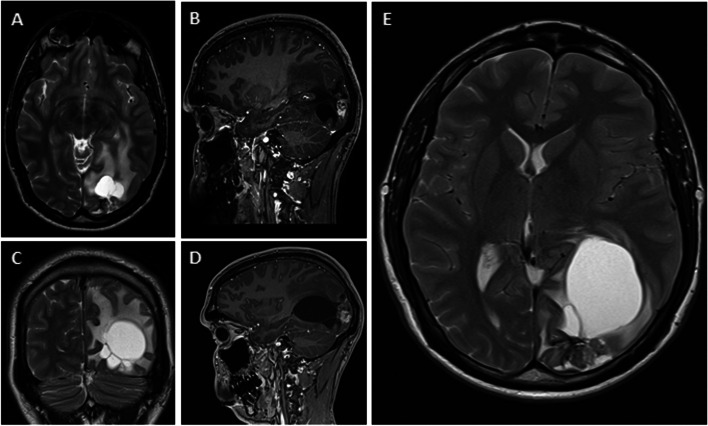

Case presentation: A case of a 28-year-old male with an increasing cyst formation (CF) appearing 10 years after SRS for AVM is presented. Despite surgical treatment, due to the incomplete resection of the angiomatous nodule, recurrence as a chronic encapsulated expanding hematoma (CEEH) occurred. This relapse required a second treatment, which could have been avoided if aggressive surgical treatment had been performed initially.